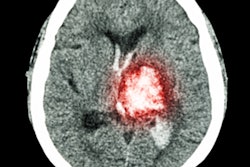

Advances in brain imaging technology may help identify more patients who are eligible for stroke treatment. Image courtesy of Dr. Gregory Albers.An ischemic stroke occurs when a cerebral blood vessel becomes blocked, cutting off the delivery of oxygen and nutrients to brain tissue. Clinicians have long thought that the area surrounding the core has the potential to be saved based on how quickly the blood flow can be restored. But over the past 20 years, researchers have been investigating whether brain imaging could detect patients with tissue that can still be salvaged by removing the blockage.

Albers and colleagues used automated software (Rapid, iSchemaView) to analyze perfusion MRI or CT scans to identify patients thought to have salvageable tissue. Study participants were randomized to receive endovascular thrombectomy -- the physical removal of the blockage -- plus standard medical therapy or medical therapy alone. Endovascular thrombectomy is currently indicated for use up to six hours following the onset of stroke.